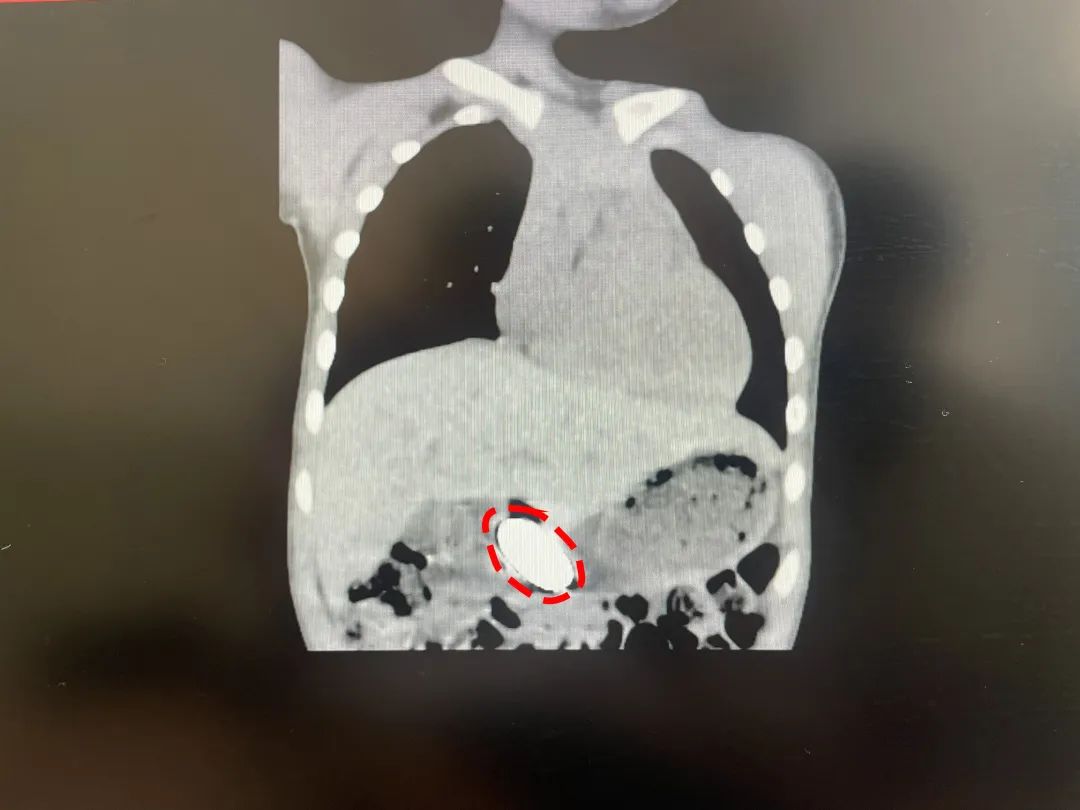

经CT检查,小明胃里存在一个4cm长的椭圆形物体,这就是他此前不小心吞下的玩具。

CT检查显示,患儿胃里存在一个4cm长的异物